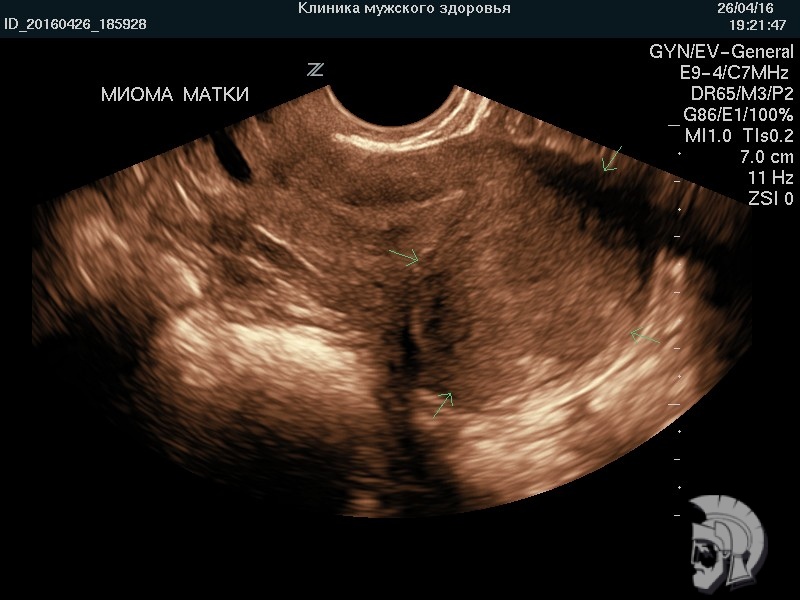

| Фото миомы матки. Крупный интерстициальный (межмышечный) узел в дне матки, деформирующий контур задней стенки |